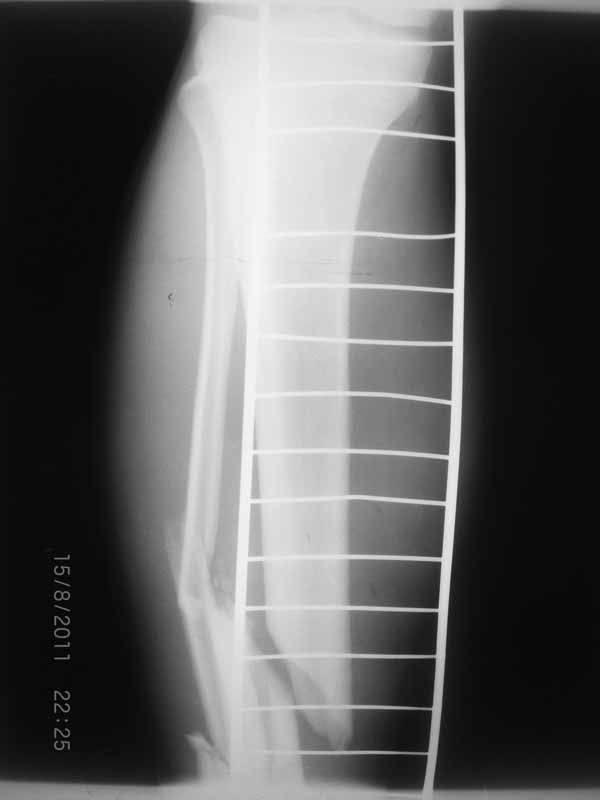

Уважаемые коллеги благодарю Вас за проявленный интерес к данной проблеме! Пересылаю Вам внешний вид правой голени.

|